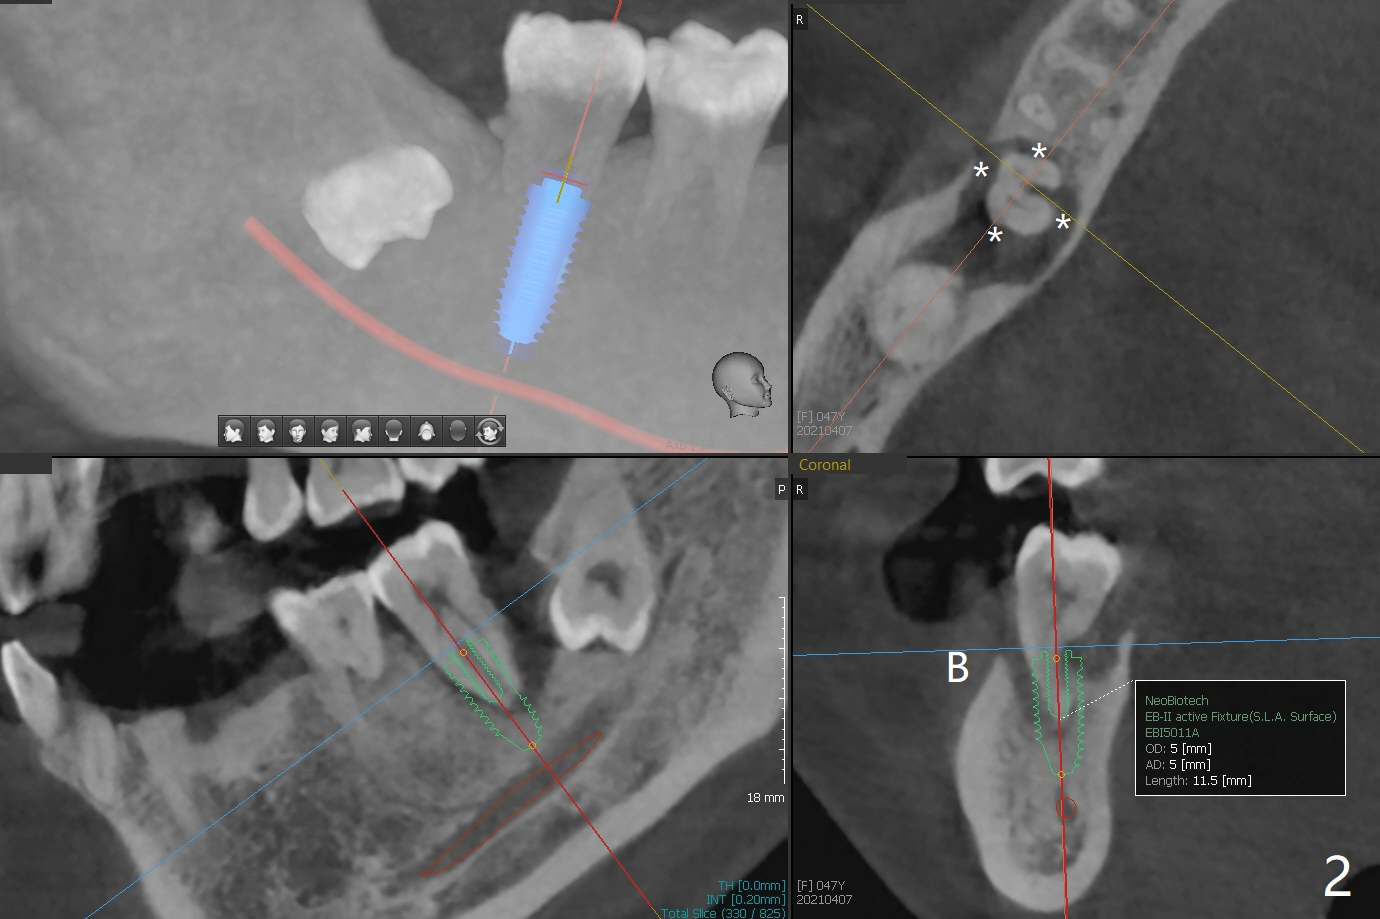

47岁女31号牙因严重牙周炎(图一)需要拔除导板即种大量植骨(图二)。炎症仿佛原发于31号牙(图二:*),为了减少创伤,选择不拔除32号牙,能行的通吗?